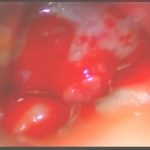

術中写真

摘出 中